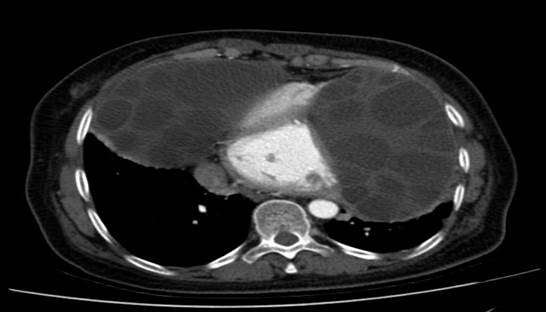

A computedtomography (CT) chest scan revealed (Figures 3-7):

• Evidence of bilaterallobar and segmental pulmonaryembolism on the right in addition to segmental pulmonary embolism localized to the leftside. The seembolic changes exhibited a chronic appearance without any indication of pulmonary parenchymal infarction. (Figures 6-7). These finding scorrelated with the observed increase in D- dimer levels.

• 2 large bilater alanterior mediastinal and para- cardiac formations, likely of hydatid origin, are

causing extrinsic compression of the cardiaccavities (Figures 3 – 5):

The structures in question are characterized by multi-walls, a regular outline, distinct margins, and an enhanced wall definition following the injection of contrast medium.

The dimensions on the right are 93 x 114 mm and extend over 119 mm;whileon the left, the measurements are 119 x 78 mm extanding over 140 mm.

Posteriorly, these structures exertcompression on the adjacent lungparenchymaresulting in passive collapse.

• Absence of pleural effusion.